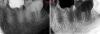

Kolchanov Опубликовано 21 февраля, 2013 Поделиться Опубликовано 21 февраля, 2013 Девушка 18 лет. Жалобы на боли от сладкого. Проходящие после устранения раздражителя. Уверенно тычет в 36. 36 представляет собой мезиальную и части щечной и язычной стенок характерного розово-бурого окраса, остальное - пломба из чего-то композитного, скорее хим отверждения. Перкуссия безболезненна, холодовая как-то неопределенно, то ли есть, то ли нет.Делаем снимок когда лечила не помнит, но в компе нашел еще один снимок с августа прошлого года. Завтра еще придет в 18.00.Прошу помочь советом.Лезть или оставить аккуратно заменив пломбу? 1 Ссылка на комментарий

anvladd Опубликовано 21 февраля, 2013 Поделиться Опубликовано 21 февраля, 2013 А мне показалось что кариес и в 5 дистально и в 7 медиально.и еще походу в7. фиссурки глубокие и уже наверняка кариес там. Фото есть? Ссылка на комментарий

Kolchanov Опубликовано 10 апреля, 2013 Автор Поделиться Опубликовано 10 апреля, 2013 Вот такая вот фигня с этим зубом получилась. Надо оно было ему, нет, теперь уже все равно.С гидороокисью в дистальном она походила с месяцок+ сегодня удалось таки залезть в мезиально-язычный. Мезиально-щечный долбил пока видел, а потом плюнул. Там и так фуркация слезами плачет, судя по снимку.Передал отправил к ортопедам. Чую штамп будет там... Ссылка на комментарий